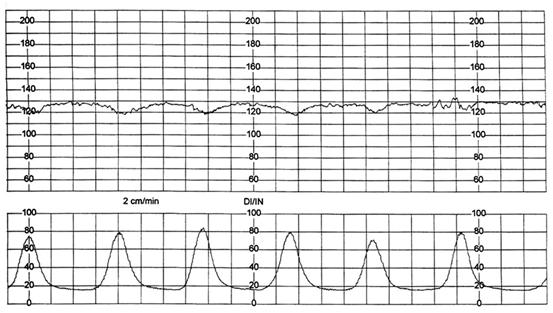

Fig. nr. 313. Pacienta M.M. - hiperkinezie la dilatatia de 5 cm, nastere pe cale vaginala, nou-nascut prematur, 2350 gr., Apgar 8/1' ( 1 cm / min )

Fig. nr. 314. Pacienta C.A., hiperkinezie uterina, nastere pe cale vaginala, nou-nascut 3600 gr, Apgar 9/1' (1 cm / min)

Trasee CTG la travalii declansate sau dirijate cu ocitocina sau prostaglandine

Travaliul declansat si/sau dirijat cu prostaglandine , respectiv ocitocina, prezinta particularitatea riscului hiperstimularii uterine cu hipertonie si hiperkinezie. Sindromul de suprastimulare se defineste ca aparitia tahisistoliei sau a hipertoniei asociata cu tahicardie fetala, deceleratii lungi sau pierderea variabilitatii bataie cu bataie. Aceste efecte secundare ale medicatiei utilizate pentru declansarea si dirijarea travaliului, creeaza conditii defavorabile intrauterine, prin scaderea fluxului placentar, cu posibilitatea aparitiei suferintei fetale .In continuare sunt prezentate cinci trasee cardiotocografice ale unor travalii declansate cu prostaglandine .